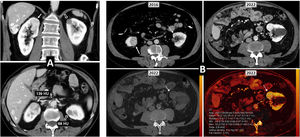

The tumours are either all benign or all malignant in 49–95% of cases, with the concordance histologically confirmed in 57–93%5 (Fig. 1), and this level is lower in more recent series. Multifocal sporadic tumours are most common in pRCC (10.9%), followed by cRCC (2%) and cRCC (1.9%).3,4,10

Multiple sporadic bilateral renal tumours that are histologically concordant. (A) Bilateral lipomas or angiomyolipomas with an almost exclusively fatty component (arrows) were found incidentally on non-contrast CT in a 65-year-old man with no other clinical or radiological features suggestive of tuberous sclerosis. (B) Bilateral papillary renal cell carcinoma (pRCC). A 78-year-old male, under follow-up for a mildly hyperattenuating left renal tumour found incidentally in a non-contrast study with low enhancement (study not shown). In the follow-up examination (left; axial composite image) moderate growth is observed (arrow), with another contralateral lesion (dashed arrow) going unnoticed. A partial left nephrectomy was performed. Image from another follow-up examination two years later (right) shows the area that underwent the partial nephrectomy (hollow arrow) and the contralateral lesion which has grown (dashed arrow). An ultrasound-guided core needle biopsy was performed. The histological result in both cases was pRCC, which was then classified as type 1. The patient opted for active surveillance, and slight growth of the right lesion was observed in the only follow-up examination, performed one year later (not shown). (B) Bilateral clear cell renal cell carcinoma (ccRCC). A 67-year-old male with haematuria. CT scan in the nephrographic phase shows an upper right renal lesion (arrows) with intense enhancement peaking in the corticomedullary phase (not shown) and central areas of necrosis, corresponding to a ccRCC pT3 pN1 after nephrectomy, and a smaller lower left lesion (arrow) with intense and slightly heterogeneous enhancement. This lesion was removed and histologically confirmed as pT1a. No germline mutation for Von Hippel-Lindau was detected and there were no other tumours in the right nephrectomy specimen. (D) Bilateral oncocytic neoplasms in a 75-year-old male. Incidental finding of two small upper lesions with moderate enhancement on average coronal image of spectral acquisition in nephrographic phase (arrows), with iodine density of 3.1 mg/mL on the iodine map of the same study in the right lesion, 4.6 in another ipsilateral lesion, and 3.2 in the left lesion (not shown). A core needle biopsy was performed on the right lesion, which resulted in an oncocytic diagnosis. The same histology was assumed for the rest of the lesions which behaved similarly. The result from the single-gene test for Birt-Hogg-Dubbé was negative. The patient opted for active surveillance.

Multiple forms of coexistence of histologically different tumours have been described 11 (Fig. 2).

Multiple sporadic bilateral renal tumours with discordant histology. (A) Contralateral clear cell (ccRCC) and papillary carcinomas (pRCC). ccRCC on right (arrows). Lesion with significant enhancement and eccentric necrotic areas on coronal and axial CT images in corticomedullary phase. pRCC on left (hollow arrows). Lesion homogeneously hypoenhancing. Arrowheads: hepatic haemangioma. (A) Contralateral ccRCC and chromophobe carcinomas. Upper left: Baseline CT (axial image in nephrographic phase). Incidental finding of well-demarcated right lower renal nodular lesion with moderate enhancement, less than that of the adjacent renal parenchyma (arrow). A contralateral cortical lesion with more intense enhancement, very similar to that of the renal parenchyma (dashed arrow) was overlooked. A right nephrectomy was performed revealing a pT1a cRCC. A review three years later revealed this lesion, with moderate growth (not shown). Six years after the first study, spectral CT was acquired (upper right: average image; lower left: virtual non-contrast image; lower right: iodine map), which again demonstrated moderate growth during the interval and iodine density of 6.8 mg/mL. Core needle biopsy revealed a pT1a ccRCC following partial nephrectomy.